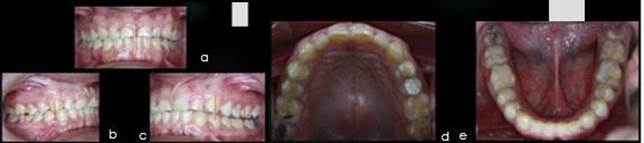

Figura 3. Fotos intrabucales, (a) frente para marcar la linea media (b, c) perfil derecho e izquierdo para marcar llave canina y relacion molar (d) oclusal superior (e) oclusal inferior. Fuente Palima(2016).

Las fotografias intrabucales son de gran ayuda para el diagnóstico de patologías en los pacientes son una herramienta útil y adicional que aporta informacion valiosa para el profesonal de la odontología, en este caso la cirugía bucal.